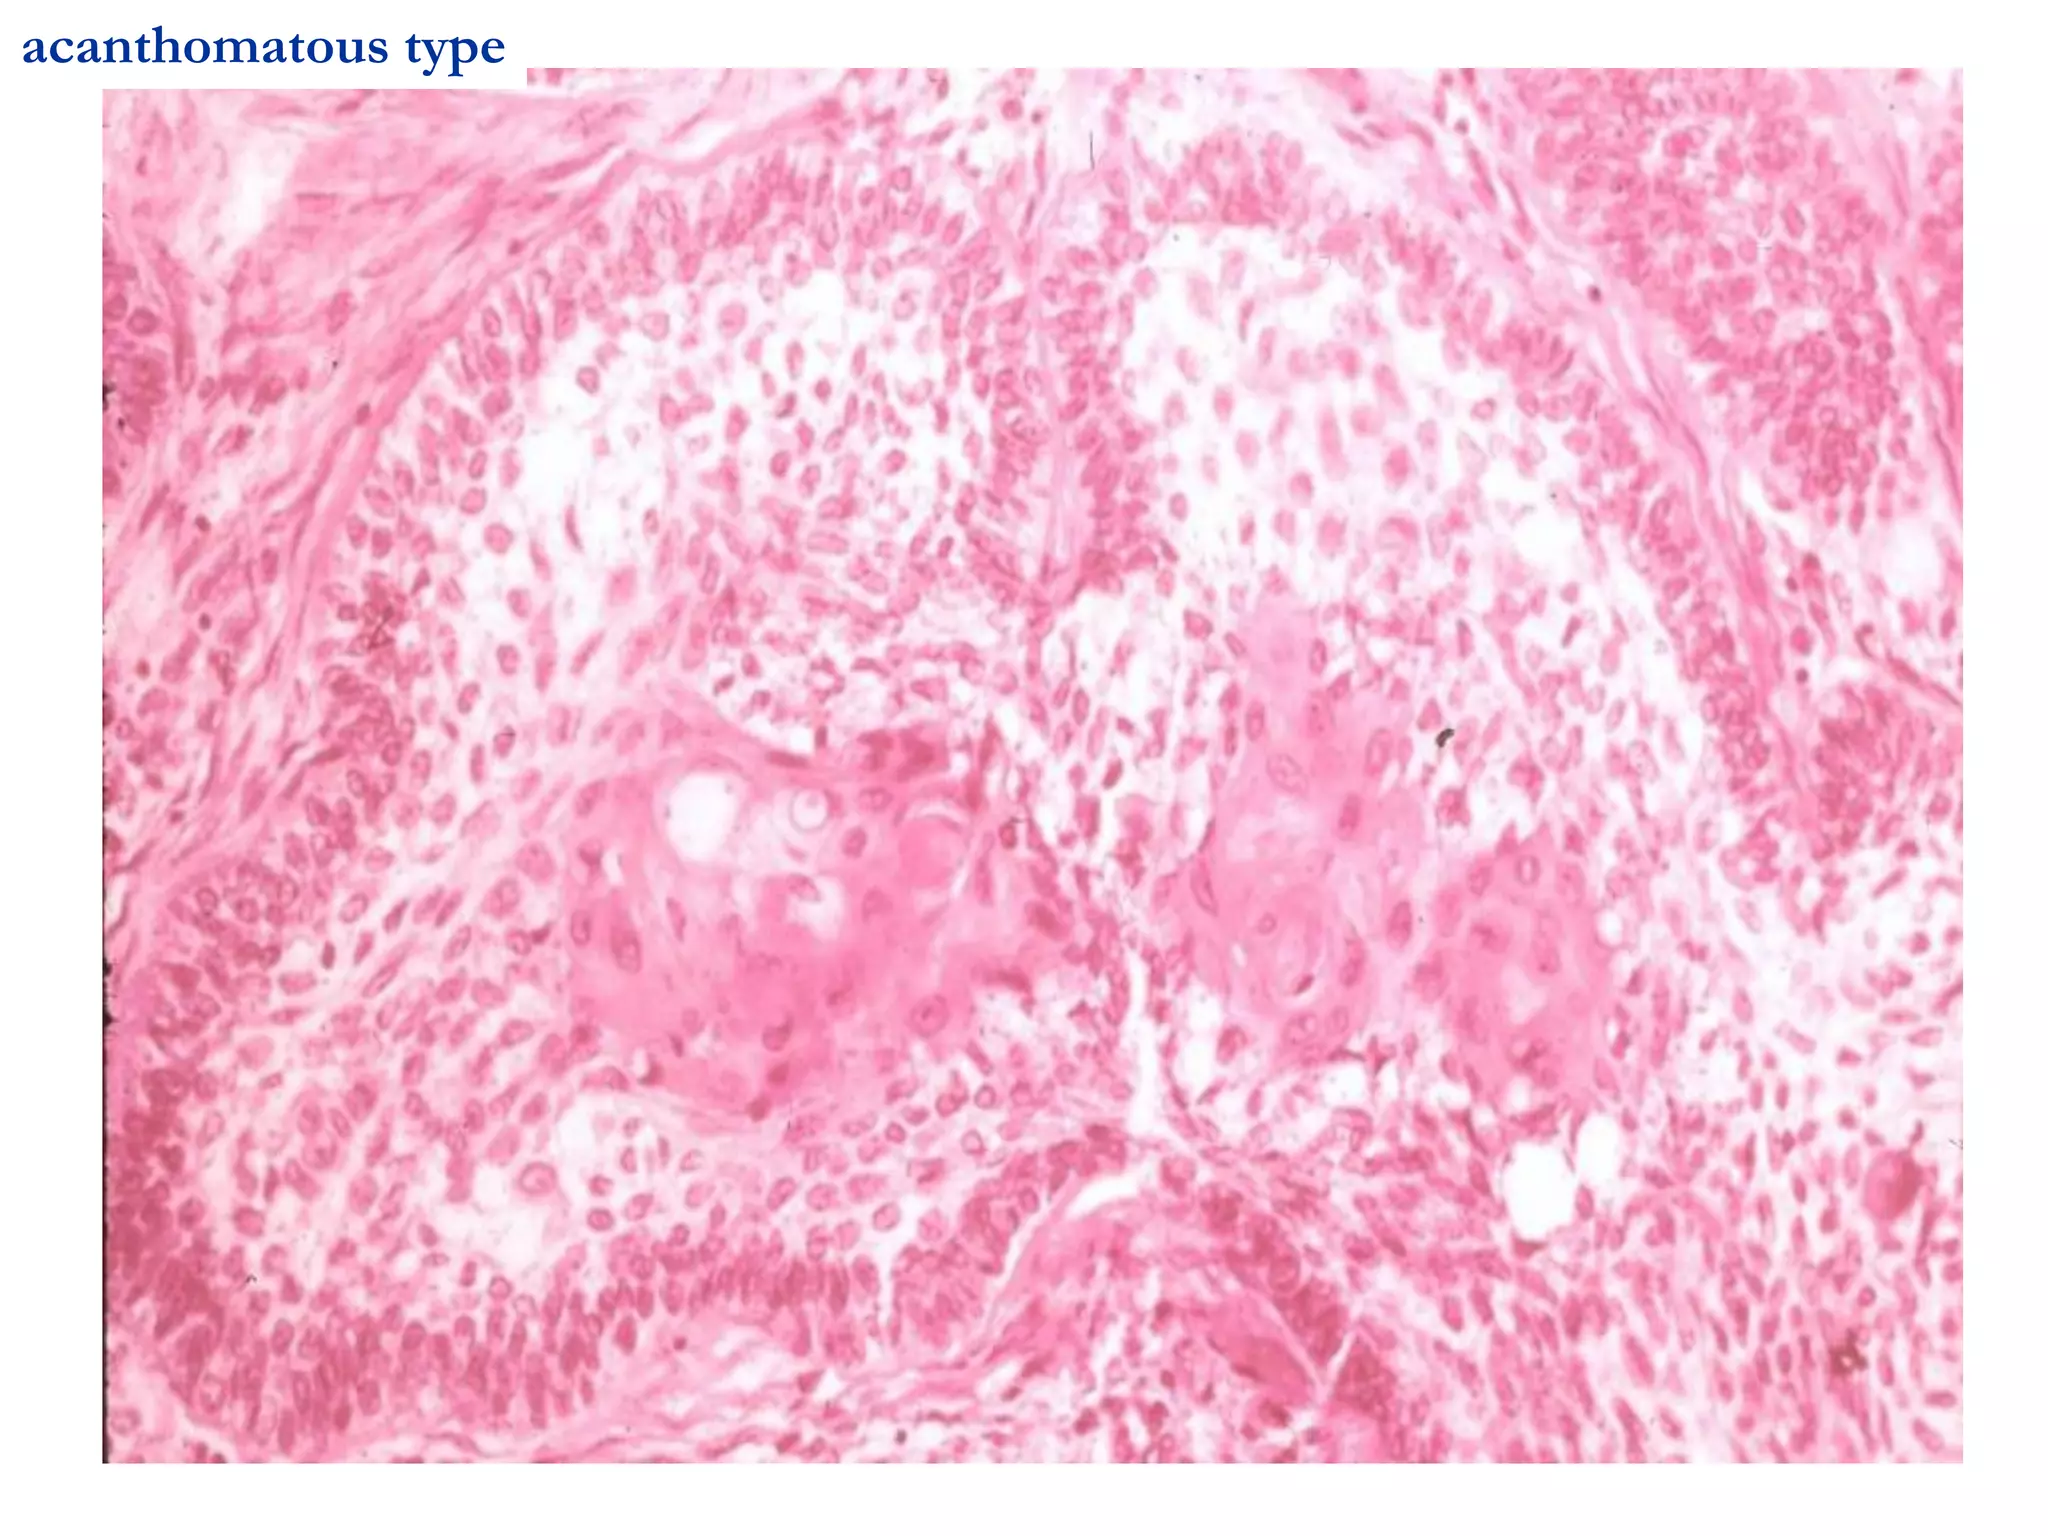

 U men ñaëc daïng u gai (acanthomatous

type) coù chuyeån saûn gai roäng, taïo chaát söøng

(keratin) trong caùc ñaûo bieåu moâ taïo raêng.